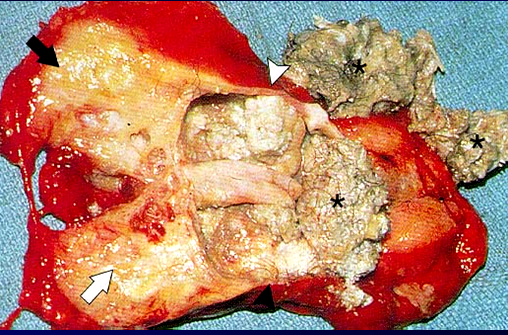

• Teratomalar həm qadınlarda, həm də kişilərdə eyni tezlikdə rast gəlinir, əksəriyyəti ön divarararlığında yerləşir və tərkibində ektodermal mənşəli toxumalar (diş, saç və sümük) rastlanır. Xoşxassəli gedişə malikdirlər, adətən AFP və betta-HCG artmır. Diaqnozunu KT ilə dəqiqləşdirmək mümkün olur (diş, kalsifikasiya). Malign potensialını nəzərə alaraq total cərrahi çıxarma tövsiyə edilir (Şəkil 24a,b,c).

Şəkil 24. Teratoma. A - KT görüntüsü

B - makropreparat

C - tərkibində ektodermal  toxumalar